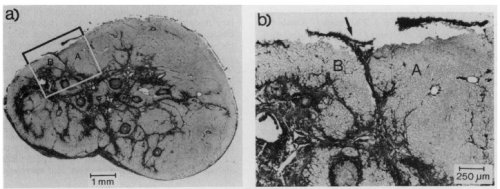

He did a extraordinary study with the scarred papillary muscle of infarcted myocardium . It included stunning histo-pathological analysis .He found for the first time , how the scar even though mechanically idle conducts in multiple directions that precipitate the arrhythmias